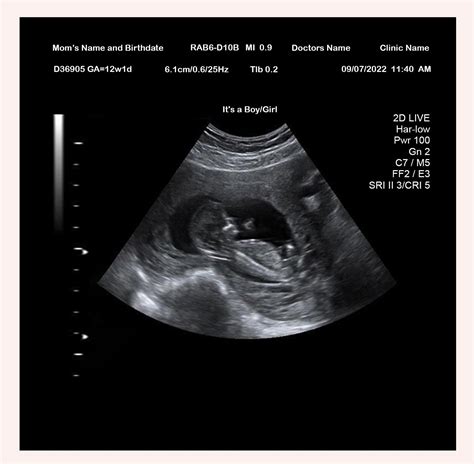

• Visualization of the Fetus: The sonographer will capture images of the fetus, including the head, abdomen, and limbs. These images help to assess the overall development and growth of the baby.

• Gestational Age: Confirmation of the baby's due date based on the measurements.

• Fetal Heartbeat: The presence and rate of the baby's heartbeat.